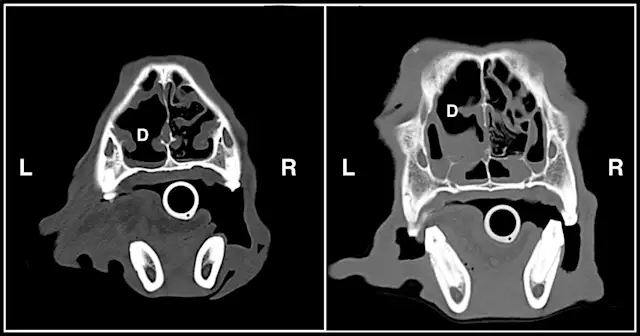

In this patient, CT (Video 1) revealed changes consistent with fungal rhinitis, including destruction of nasal turbinates and lesser flat bone destruction without evidence of a soft tissue mass (Figure 1) and irregular noncontrast-enhanced material in the frontal sinus, along with hyperostosis of the frontal bone (Figure 2).

Figure 1.

Two CT slices at different levels through the nasal cavity showing cavitated lesions secondary to turbinate destruction (D) in the left nasal cavity. There are milder changes in the right nasal cavity. (L = left, R = right)

For comparison, Video 2 shows CT of a dog with chronic rhinitis. Some patchy soft tissue/fluid density can be seen in the region of the nasal turbinates. However, no significant bony destruction is evident, nor is there any opacity within the frontal sinuses or frontal bone sclerosis.